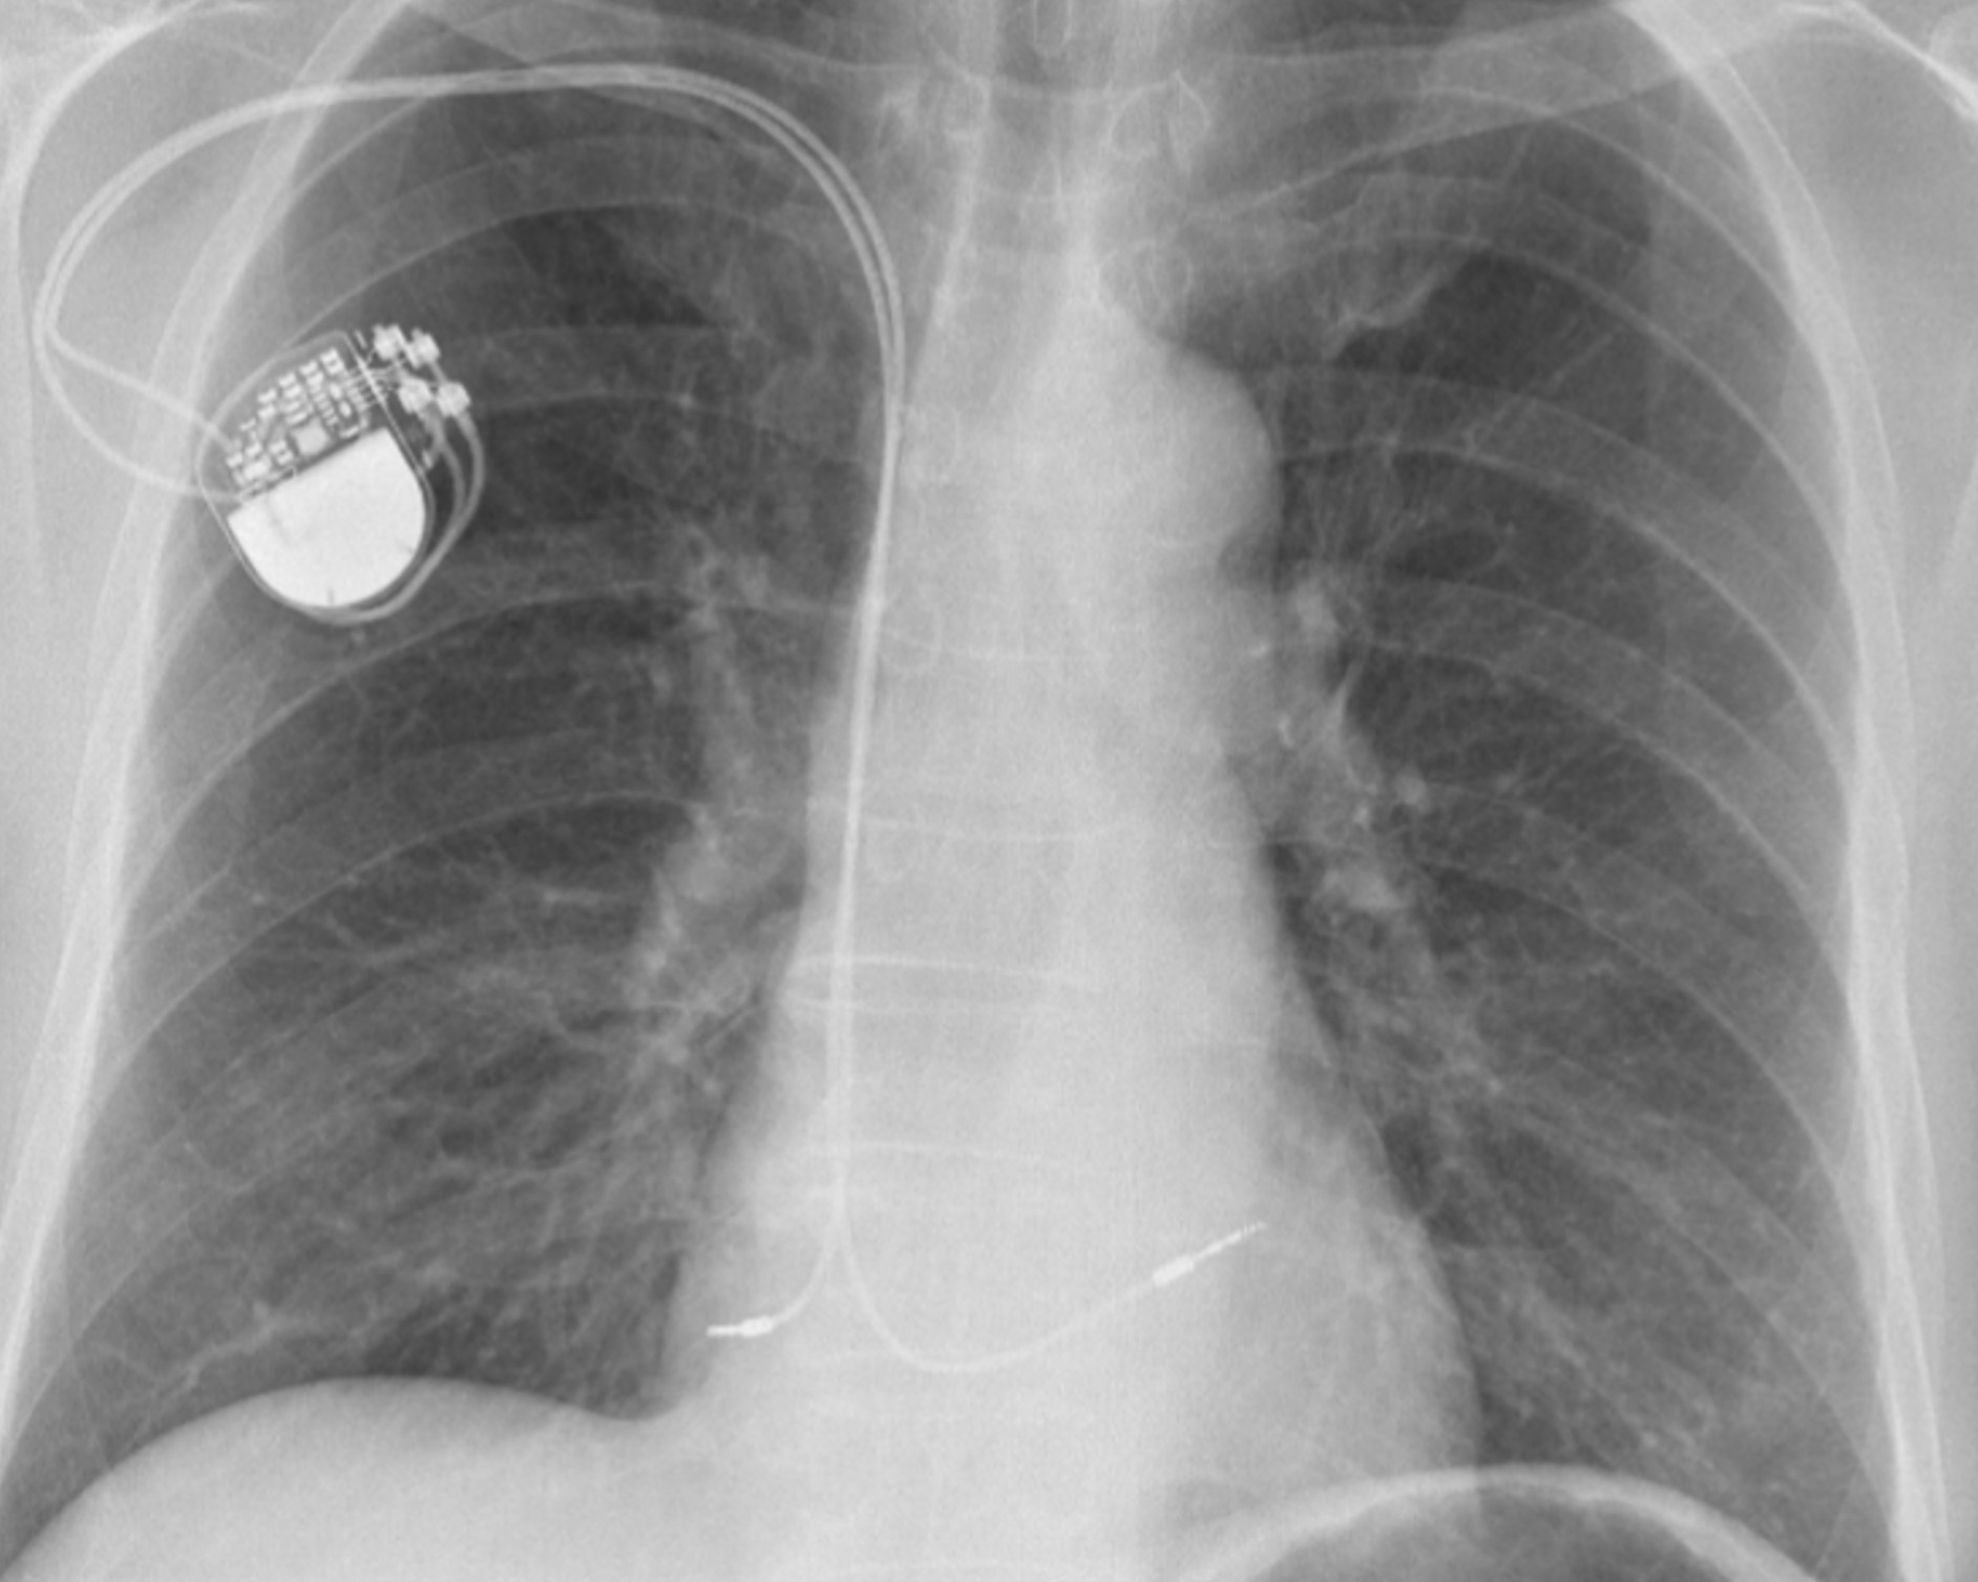

Künstliche Intelligenz: Entwicklung einer Applikation um Röntgenbilder mit Künstliche Intelligenz auszuwerten. Dabei wurde das System von Ärzten angelernt. Geplantes «Going Live» Q1 2021.

Weltweit präsent, doch zuhause in Küssnacht. Es macht uns Stolz, dass unsere Kardiologie Software auch in Bangladesch sehr gefragt ist.